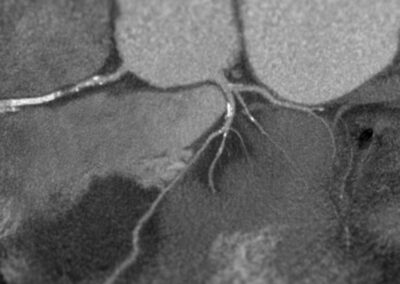

στεφανιογραφία στον αξονικό τομογράφο.

Τρισδιάστατη και δισδιάστατη απεικόνιση των στεφανιαίων αγγείων όπου διακρίνεται σημαντικότατη στένωση της δεξιάς στεφανιαίας αρτηρίας λίγο πριν το προϋπάρχον stent, το οποίο απεικονίζεται φυσιολογικά βατό